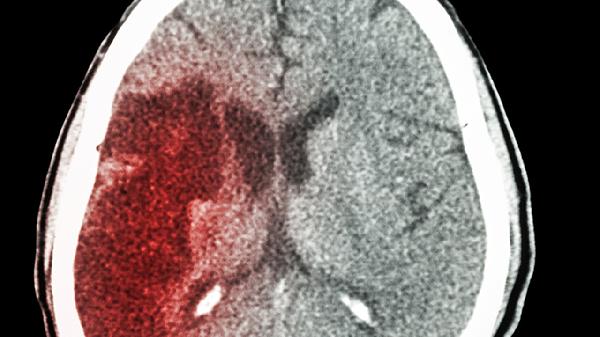

女子确诊脑梗后20年无复发,医生直言:6个好习惯值得借鉴!

凌晨三点,救护车的警笛声划破夜空,45岁的张女士被紧急送医——突发脑梗。20年后的今天,这位曾经的病友不仅行动自如,连主治医生都惊叹她的恢复状况。翻开她的健康日记,六个看似平常的生活细节,藏着对抗脑梗的"金钥匙"。